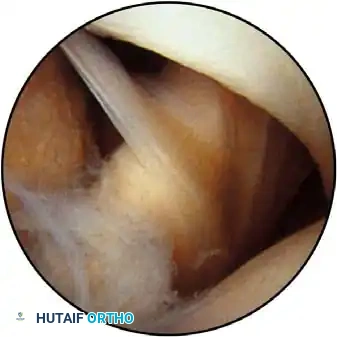

Routine diagnostic arthroscopy is performed using a 4-mm, 30-degree oblique arthroscope. This angle allows for comprehensive visualization of the entire joint through rotation of the lens and manipulation of the arm. In complex instability cases, switching to a 70-degree arthroscope dramatically improves visualization of the anterior glenoid neck and the inferior glenohumeral ligament, which is critical during arthroscopic capsulorrhaphy.

Once diagnostic evaluation is complete and hemostasis is secured, the therapeutic phase commences. Whether performing a SLAP repair, a Bankart stabilization, or a rotator cuff repair, the principles of tissue mobilization, anatomical footprint restoration, and secure biomechanical fixation remain paramount.

Modern arthroscopy relies heavily on suture anchors (biocomposite or all-suture constructs) and advanced arthroscopic knot-tying or knotless techniques. The ability to pass sutures through retracted, fibrotic tissue and secure them under appropriate tension without strangulating the microvascular supply is the hallmark of a master arthroscopist.